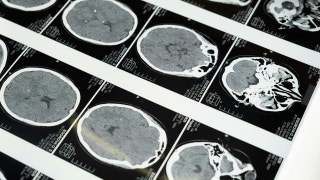

Fox News Flash top headlines are here. Check out whats clicking on FoxNews.com. In the near future, keeping tabs on your digestive health may feel far less intimidating. Instead of booking a procedure that requires prep, sedation and time away from work, you could swallow a small capsule loaded with sensors and microelectronics. As it moves through your gastrointestinal tract, the capsule can gather data on inflammation, tissue integrity and suspicious changes. It then sends that information wirelessly to your doctor for review. Scientists are building these ingestible devices to do more than observe. Some prototypes are designed to release medication at an exact location inside the gut. Others are being developed to collect tiny tissue samples before passing naturally from the body. The technology is still advancing, but momentum is clearly building. Sign up for my FREE CyberGuy Report Get my best tech tips, urgent security alerts, and exclusive deals delivered straight to your inbox. Plus, you’ll get instant access to my Ultimate Scam Survival Guide — free when you join my CYBERGUY.COM newsletter. UC Irvine researchers discovered how fiber reshapes gut bacteria to block sugar’s harmful effects. (iStock) Gastrointestinal conditions affect millions of people each year. Diagnosing them often involves blood tests, imaging scans and invasive procedures like endoscopy. Endoscopy remains an essential tool. However, it requires sedation and can be uncomfortable. It also has limits, especially when doctors need to examine deeper sections of the small intestine. Capsule endoscopy helped bridge that gap. Devices such as PillCam allow doctors to view images from inside the digestive tract without threading a scope through the entire system. Still, most existing capsules are passive. They capture images or data, but they do not respond dynamically to what they detect. That is where smart pill technology begins to stand apart. Capsule endoscopy devices like PillCam allow doctors to view the digestive tract without invasive scopes or sedation. (Medtronic) Engineers are now building capsules that sense chemical and physical changes inside the gut. At the University of Maryland, College Park, researchers are developing devices that measure bioimpedance. This method evaluates how electrical signals move through intestinal tissue. When inflammation alters the gut lining, those electrical patterns shift. By detecting these subtle changes, a smart pill may provide early clues about conditions such as inflammatory bowel disease. Instead of waiting for severe symptoms, doctors could identify problems sooner. Earlier detection often leads to more effective treatment and better long-term outcomes. Researchers are also studying ways to monitor enzymes and other biomarkers that could signal pancreatic disorders or early-stage cancer. Many drugs used to treat GI disorders circulate throughout the entire body. While they can help, they may also cause side effects in areas that are not diseased. Smart capsules offer a more targeted approach. Some experimental designs include tiny mechanical systems that deploy microscopic needles. These systems can release medication directly into the intestinal lining. Other designs anchor a dissolvable drug payload at a specific site. The medication then releases slowly over time in that exact location. Targeted delivery could reduce overall drug exposure and improve effectiveness. For patients who struggle with side effects, that shift could be significant. Biopsies remain a cornerstone of many gastrointestinal diagnoses. Traditionally, doctors collect tissue samples during endoscopy. Engineers are now exploring swallowable capsules with built-in mechanical systems capable of collecting small samples of tissue. Some prototypes rely on spring-loaded mechanisms that activate wirelessly. A tiny internal heater releases stored energy, which powers a miniature cutting tool. After collecting the sample, the capsule seals it safely inside. The device then continues its journey through the digestive tract and exits naturally. The engineering challenges are substantial. The device must generate enough force to collect tissue while remaining small and safe to swallow. Power is one of the biggest hurdles in ingestible electronics. Many capsules depend on small coin cell batteries, which can occupy a large portion of the internal space. Researchers are investigating alternatives. Some teams are studying microbial fuel cells that generate electricity using bacteria in the gut. Others are testing chemical reactions with stomach fluids to produce energy. Every solution must prioritize safety, reliability and biocompatibility. The capsule has to survive stomach acid and digestive enzymes while maintaining stable performance. AI WEARABLE HELPS STROKE SURVIVORS SPEAK AGAIN Researchers and clinicians are working to turn these swallowable devices into tools that diagnose disease and deliver targeted treatment. (Kurt "CyberGuy" Knutsson) Despite the promise, ingestible smart pills must clear strict regulatory standards before becoming widely available. Capsules must prove they will not become lodged in the intestine or damage tissue. Their materials must remain stable inside a harsh chemical environment. Wireless signals must stay safe and reliable. Clinical trials will determine whether these devices improve outcomes compared with existing tools. Progress is steady, but careful testing remains essential. If smart pill technology continues to advance, it could change how you experience digestive care. Routine monitoring might require nothing more than swallowing a capsule at home. Doctors could receive detailed data without scheduling invasive procedures. Targeted drug delivery could mean fewer systemic side effects. Screening may also become more accessible. According to the American Cancer Society, many eligible adults are not up-to-date on colorectal cancer screening. Less invasive tools could encourage more people to participate. That matters. Earlier detection saves lives. Take my quiz: How safe is your online security? Think your devices and data are truly protected? Take this quick quiz to see where your digital habits stand. From passwords to Wi-Fi settings, you’ll get a personalized breakdown of what you’re doing right and what needs improvement. Take my Quiz here: Cyberguy.com. Electronics that you can swallow are moving from research labs toward clinical testing. The goal is straightforward. Make diagnosis less invasive. Make treatment more precise. Reduce the burden of repeated procedures. The digestive tract holds valuable clues about your overall health. Smart pills could provide doctors with new ways to access that information without putting patients through traditional scopes and sedation. If a small capsule could monitor your gut, deliver medication and potentially detect cancer earlier, would you trust it enough to swallow it? Let us know by writing to us at Cyberguy.com. CLICK HERE TO DOWNLOAD THE FOX NEWS APP Sign up for my FREE CyberGuy Report Get my best tech tips, urgent security alerts, and exclusive deals delivered straight to your inbox. Plus, you’ll get instant access to my Ultimate Scam Survival Guide — free when you join my CYBERGUY.COM newsletter. Copyright 2026 CyberGuy.com. All rights reserved. Kurt "CyberGuy" Knutsson is an award-winning tech journalist who has a deep love of technology, gear and gadgets that make life better with his contributions for Fox News & FOX Business beginning mornings on "FOX & Friends." Got a tech question? Get Kurt’s free CyberGuy Newsletter, share your voice, a story idea or comment at CyberGuy.com. Get a daily look at what’s developing in science and technology throughout the world. Subscribed You've successfully subscribed to this newsletter!